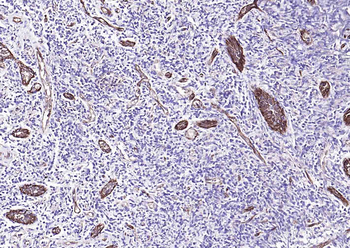

Immunohistochemical staining of paraffin embedded rat brain tissue using CD31 antibody (primary antibody at 1:100)

Immunohistochemical staining of rat heart tissue using anti-CD31 (primary antibody at 1:100)